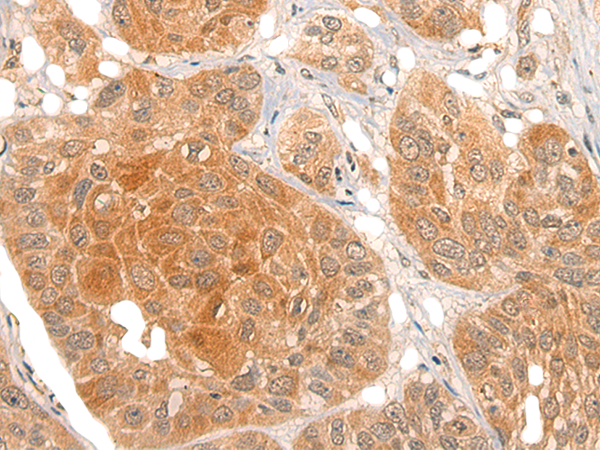

分类: 科研抗体货号: P13182别名: CIAB1; TAOS1; ORAOV1应用: IHC反应种属: Human